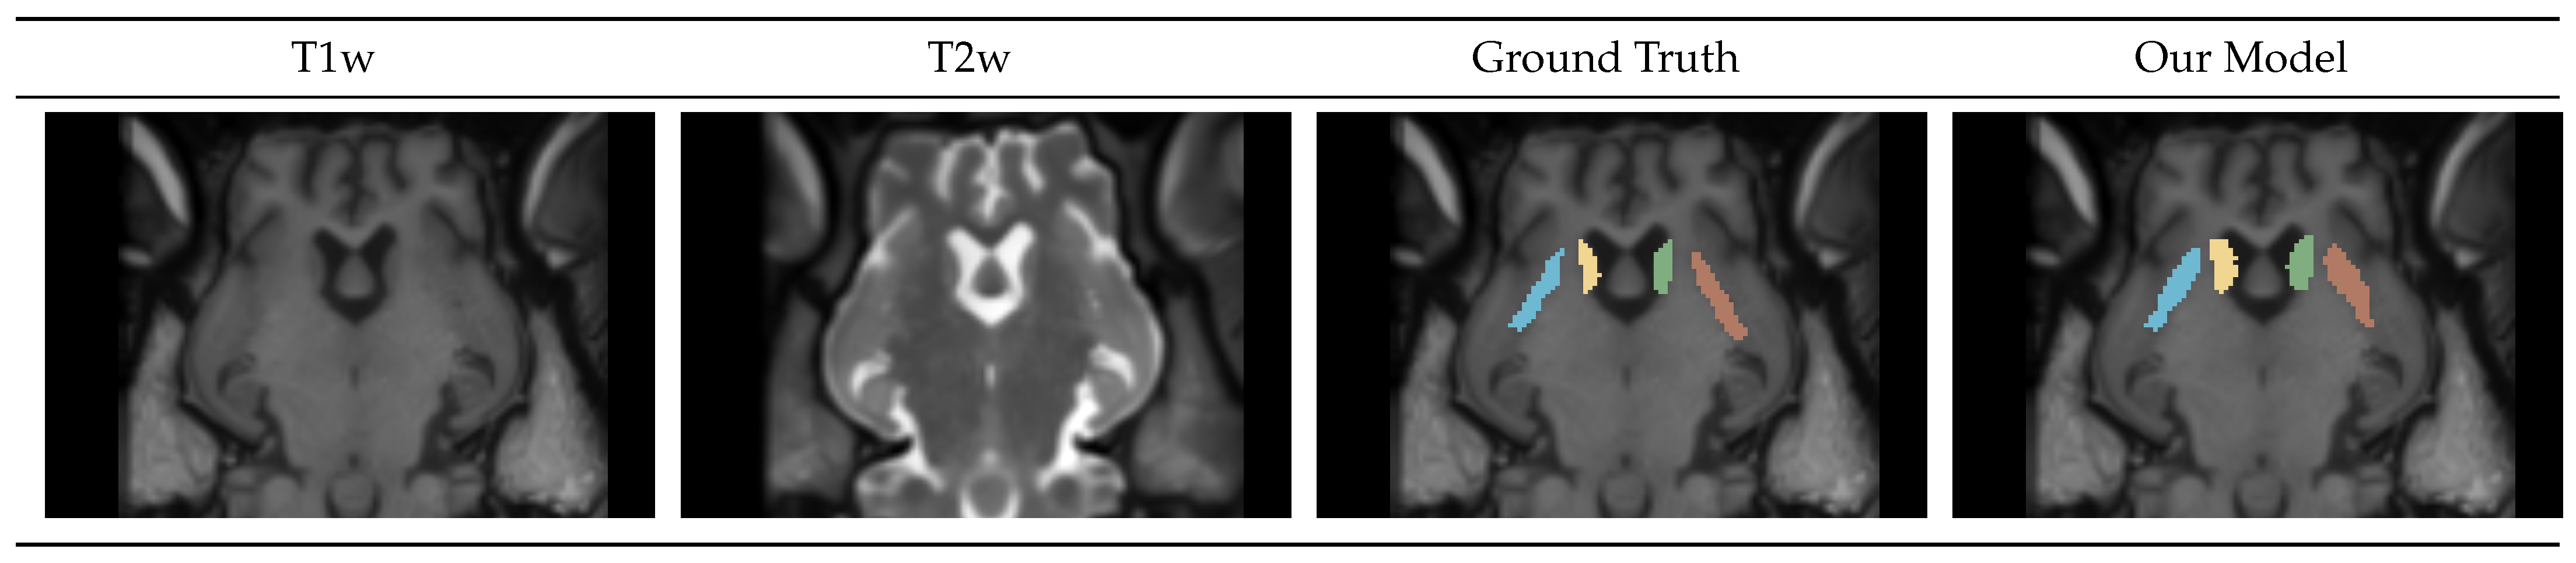

4.1.3. Caudate-Putamen Segmentation Mask

4.1.4. Gray-White-CSF Segmentation Mask